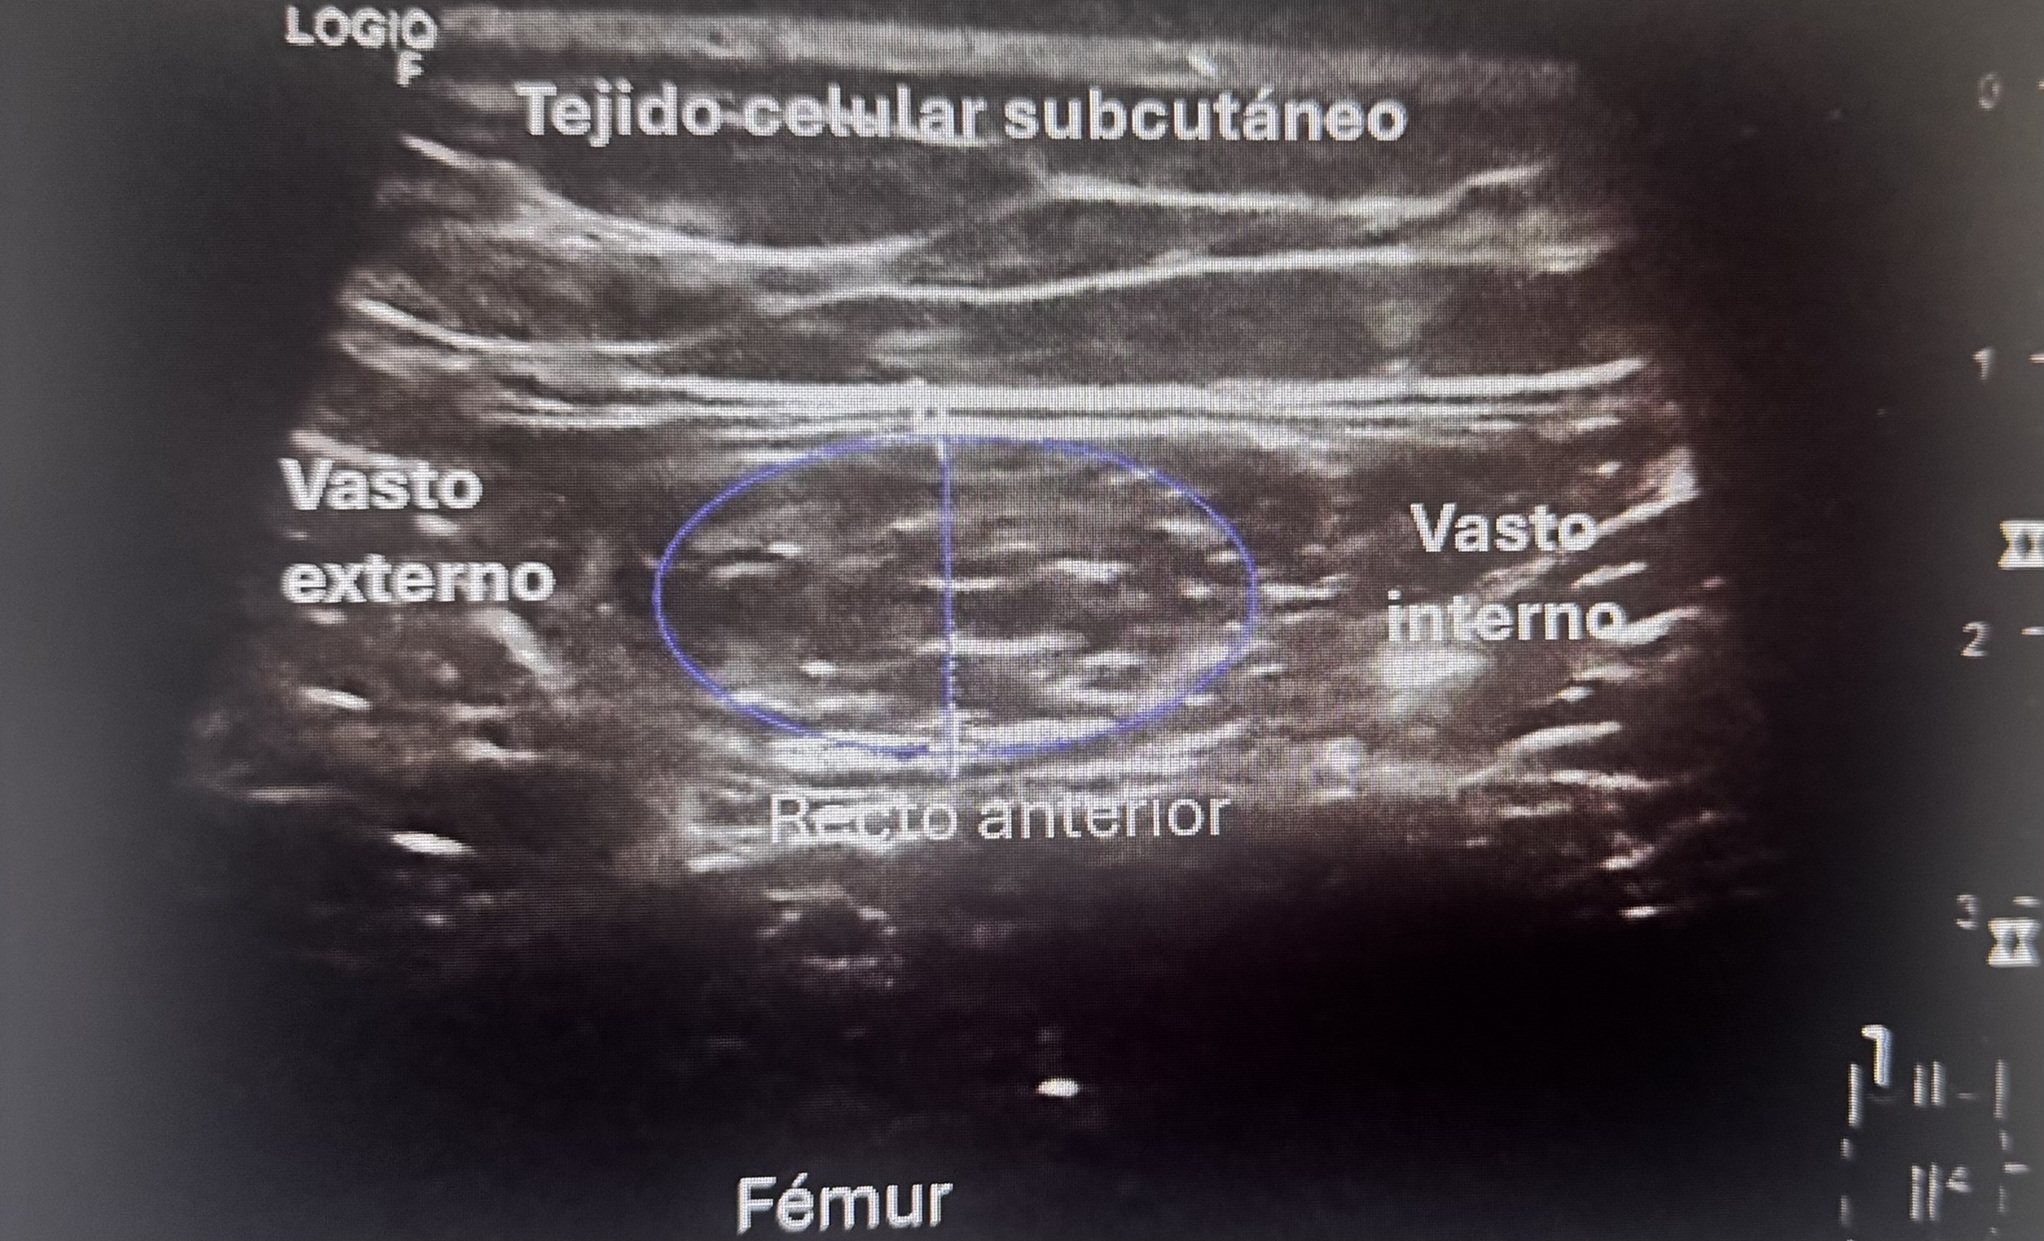

Caso 2. Sarcopenia Obesiva (54 años). Hombre obeso (IMC 46,4 kg/m2) en tratamiento farmacológico desde junio, con debilidad muscular progresiva. Eco de recto anterior del cuádricep: espesor muscular reducido (eje corto 10,5 mm) con infiltración grasa, compatibles con sarcopenia obesiva. Diagnóstico: mala distribución adiposa con pérdida de masa muscular de calidad. Intervención: entrenamiento resistencia supervisado, proteína aumentada (1,2 g/kg), suplementación con vitamina D. Reevaluación a 4 meses.